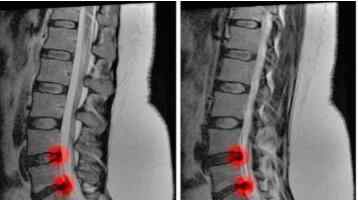

大腿后侧疼痛可能是由于腘绳肌损伤,L5-s1椎间盘突出压迫s1神经,或梨状肌压迫坐骨神经所致。

大腿外侧疼痛可以是髂胫束的张力性疼痛,也可以是L4-5椎间盘突出压迫L5神经引起的放射痛,也可以是臀中肌压迫神经的张力性疼痛!

大腿前侧疼痛可以是股四头肌损伤,L3-4椎间盘突出压迫L4神经,也可以是股前外侧皮神经压迫引起的放射痛!